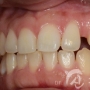

치간이개 치료사례